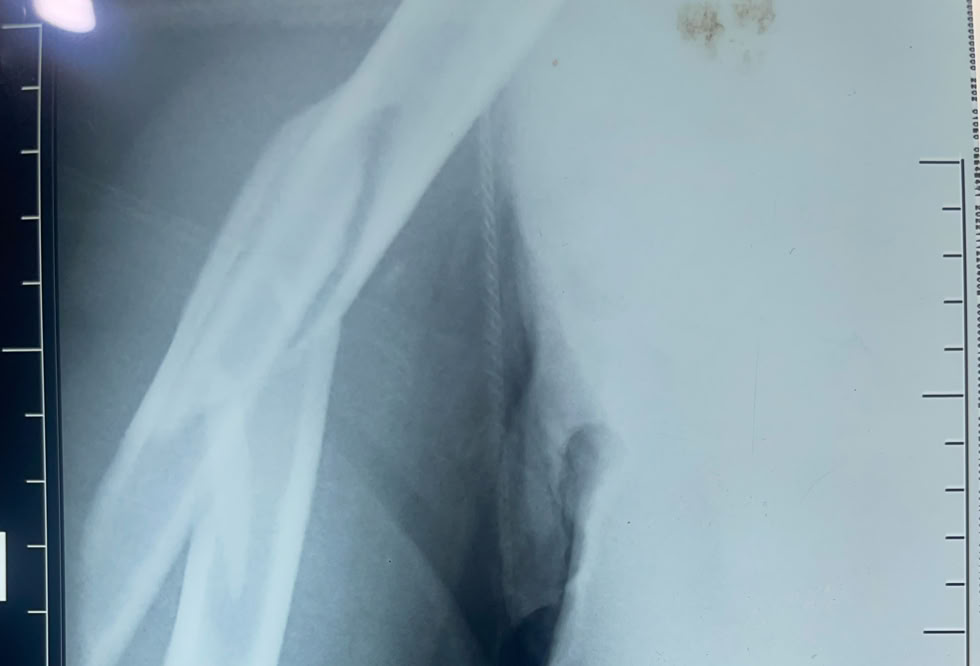

Recibimos la visita de un traumatologo que trabaja en un hospital de Duala y que se desplazó hasta Dschang para que le tratáramos nosotros las lesiones que sufrió al caerse por unas escaleras, “no se fiaba de sus compañeros de hospital”. Una fractura de la extremidad distal del radio que solucionamos con una reducción y estabilización con agujas K (no tenemos placas volares) con excelente resultado  y una fractura diafisaria de humero que solucionamos con unos clavos elásticos (no tenemos clavos de humero). El paciente estaba muy satisfecho a pesar de la parálisis radial que se produjo al fracturarse.